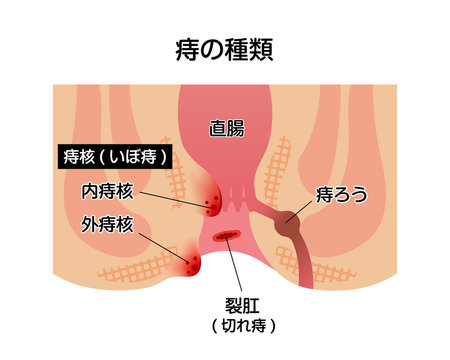

おしりの構造と病気 森外科医院 日本大腸肛門病学会認定施設 日本臨床肛門病学会認定施設 岐阜県大垣市で肛門科をお探しの方は肛門専門病院の森外科医院までご相談下さい

痔について 門田外科医院

痔ってなンだ 4 おしりだって風邪をひく

あなたの痔はどのタイプ 診療方法と肛門科診療のタイミング 内科 整形外科 肛門科 痔 浜中医院 大阪府岸和田市

肛門に多い病気

痔 肛門 断面図 イラスト素材 フォトライブラリー Photolibrary